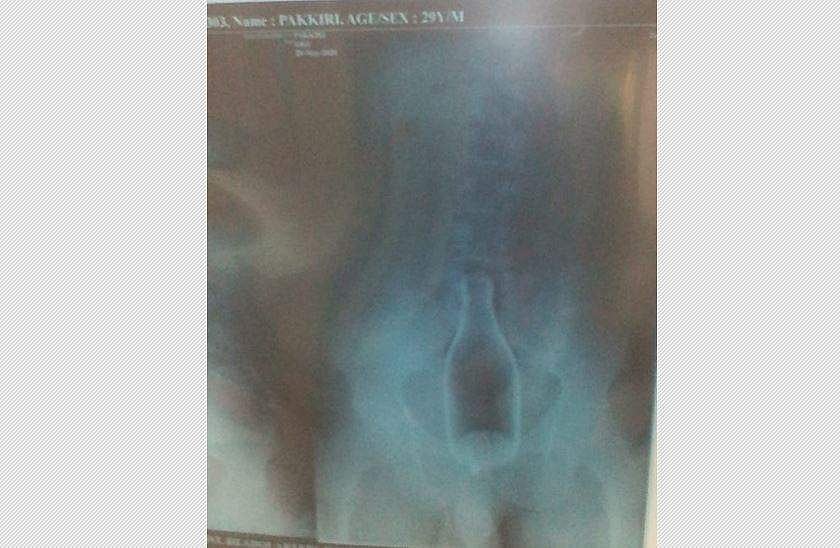

அங்கு அவருக்கு மேற்கொள்ளப்பட்ட ஸ்கேன் பரிசோதனையில், பக்கிரிசாமியின் வயிற்றில் ஒரு பாட்டில் முழுமையாக சிக்கியிருப்பது தெரியவந்தது. இதையடுத்து, மருத்துவர்கள் சிறிய அளவிலான அறுவைச் சிகிச்சையும், மலக்குடலை சுத்தம் செய்யும் இனிமா சிகிச்சையும் அளித்து, அவரது வயிற்றில் இருந்த பாட்டிலை அகற்றினர்.